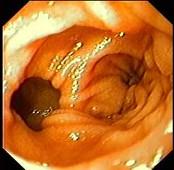

问题 女性,45岁。腹部饱胀不适2年余。表情自然,皮肤无黄染,未见蜘蛛痣,巩膜无黄染。腹平坦,腹肌软,全腹无压痛反跳痛,肝脾肋缘下0.5cm,胃镜检查如下图,诊断为 ( )

选项 A、十二指肠穿孔 B、十二指肠雍滞症 C、十二指肠溃疡 D、十二指肠炎 E、十二指肠憩室

答案 E